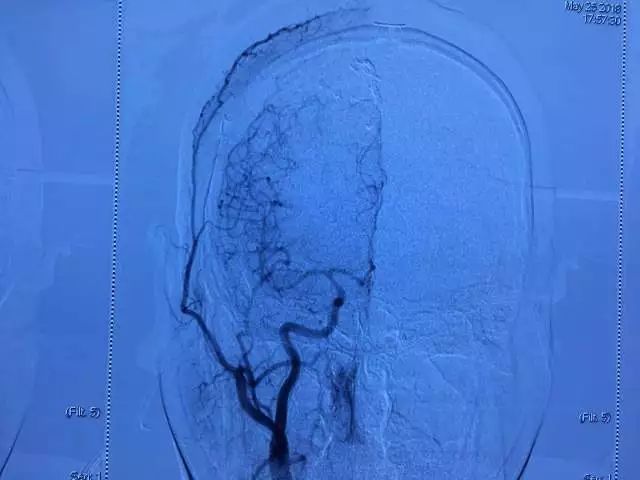

▲ 术前DSA

术后复查DSA

血管畸形并血流现相关性动脉瘤全切